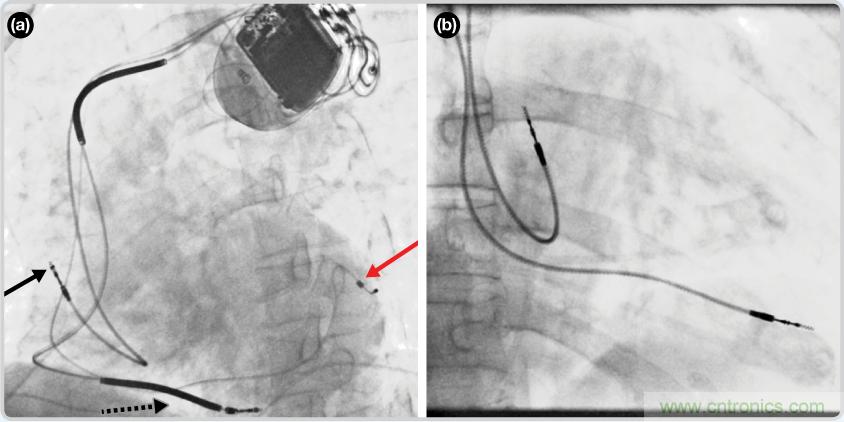

CRT器件在圖4(a)中的透視圖像中可以看見。醫(yī)師就是利用這種影像來放置導(dǎo)聯(lián)線的。對(duì)于非專業(yè)人士來說,這種影像是很難解讀的??梢钥吹叫呐K淡淡的輪廓——這是搏動(dòng)中的心臟的靜態(tài)視圖。起搏器位于右心房上,心臟頂點(diǎn)指向右下方。在這個(gè)典型的導(dǎo)聯(lián)線放置實(shí)例中,黑色箭頭指向右心房導(dǎo)聯(lián)線。虛線黑色箭頭指向右心室導(dǎo)聯(lián)線。紅色箭頭標(biāo)示的導(dǎo)聯(lián)線只能看到一部分,這是左心室導(dǎo)聯(lián)線(紅箭頭指向電極尖端)。圖4(b)展示的是雙腔起搏器的典型導(dǎo)聯(lián)線放置透視圖像。右心房導(dǎo)聯(lián)線指向上方,置于右心房中。右心室導(dǎo)聯(lián)線則位于右心室頂部。

圖4. 起搏器導(dǎo)聯(lián)線放置的透視圖像3 (a). 單腔起搏器;(b).雙腔起搏器